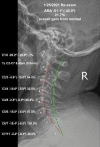

We present the case of a patient receiving structural rehabilitation following a rear-impact motor vehicle collision (MVC). Medications did not alleviate the symptoms of the crash injuries. Resolution of injury-caused pain and disability was found following postural and structural rehabilitation treatment. A 39-year-old male was injured in a rear-impact collision between two very large vehicles. Severe migraine headaches, neck pain, and radiculopathy, as well as lower back pain, were the result of the crash. Patient-reported outcomes (PROs) demonstrated that the symptoms were causing severe disability and poor health-related quality of life (HRQoL) measures. Radiographs found spine alignment abnormalities consistent with rear impact MVC. Chiropractic Biophysics® (CBP®) structural rehabilitation was performed. Following a treatment regimen involving strengthening weakened and damaged muscles, postural and spinal traction, postural spinal manipulative therapy (SMT), and home therapies resulted in the resolution of the symptoms. All outcome measures demonstrated improvement, including Short-Form 36 question health questionnaire (SF-36), quadruple visual analog scale (QVAS), headache disability index (HDI), neck disability index (NDI), revised Oswestry disability index (RODI), as well as significant measured improvements found on radiographs. Spine pain and altered alignment are frequent results of MVCs. If left uncorrected, these abnormalities increase the likelihood of chronic pain and disability. Combined low back pain (LBP), neck pain (NP), headache (HA), and radiculopathy, as found in our subject, significantly pre-dispose the individual to poor HRQoL, years lived with disability (YLDs) and increased the global burden of disease (GBD). Physicians who treat injured patients should have a repeatable, reliable, valid, and efficacious method to reduce pain, increase range of motion (ROM), improve spine alignment, and improve the performance of activities of daily living (ADLs). Further, larger studies of injured patients are necessary to determine if the CBP® protocol reduces GBD caused by MVC injuries.